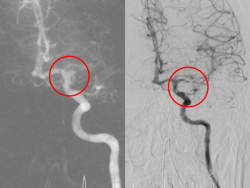

左圖為急性大腦動脈栓塞(缺血性腦中風),右邊為施行顱內動脈取栓手術,移除血栓讓血流恢復正常 【News586/記者張淑慧報導】高雄一名70多歲的潘奶奶在清晨起床時發現左手左腳無法動彈,左半身乏力且說話口齒不清,家人立即將她送往小港醫院急診。經電腦斷層檢查,確診為急性大腦動脈栓塞(缺血性腦中風),符合進行「顱內動脈取栓手術」的適應症。在家人商討後,潘奶奶決定接受神經導管介入治療。醫院...... [閱讀更多]